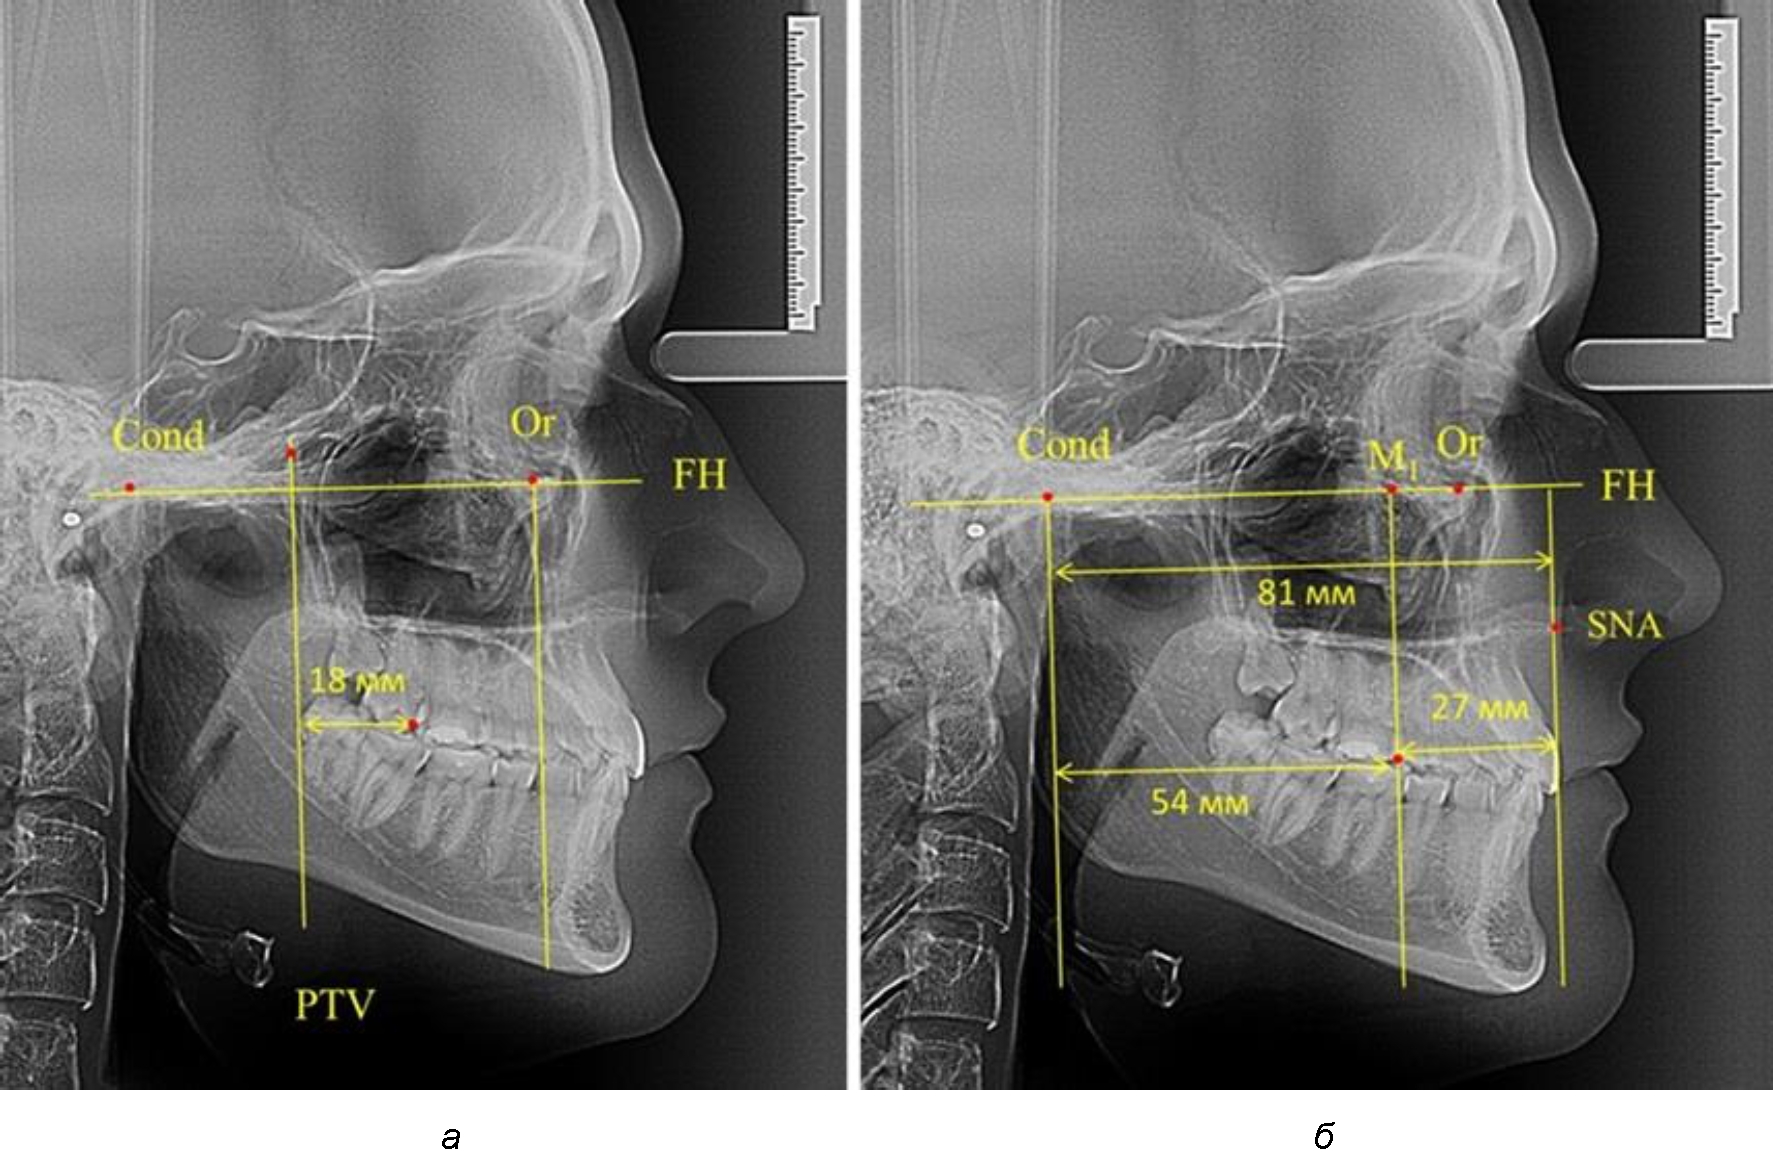

При проведении анализа к Франкфуртской горизонтали проводили передний и задний перпендикуляры. Передний спинальный перпендикуляр проходил через выступающую точку передней носовой ости (spina nasalis anterior – SNA), а задний суставной перпендикуляр опускали из кондилярной точки Cond. Молярный перпендикуляр проводили через медиальную поверхность первого постоянного моляра. Указанная вертикаль отделяла замещающие зубы постоянного прикуса от добавочных зубов (постоянных моляров), что вполне логично для анализа положения первых постоянных моляров в гнатическом комплексе (рис. 1).

Рис. 1. Метод определения положения первых верхних моляров по Ralph E. McDonald (а) и по предложенному методу (б)

Анализ проведенного исследования рентгенограмм показал существенную вариабельность практически всех линейных показателей. У молодых людей с физиологическим прикусом постоянных зубов расстояние от крыловидной вертикальной плоскости PTV до дистальной поверхности верхнего первого постоянного моляра в целом по группе составляло (18,37 ± 3,62) мм. Обращает на себя внимание большая ошибка репрезентативности из-за разницы между максимальными и минимальными значениями.

Среди анализируемых рентгенограмм минимальное значение расстояния по методу R. E. McDonald было 12 мм, а максимальное достигало 25 мм, что, по нашему мнению, обусловлено вариабельностью сагиттального размера гнатического отдела лица.

Среднее расстояние между суставной (кондилярной) и спинальной вертикалями в анализируемой группе составило (89,12 ± 2,8) мм. При этом сагиттальный размер в среднем составлял (58,74 ± 1,57) мм, а передний размер был (30,41 ± 1,02) мм. Несмотря на вариабельность размеров и большую ошибку репрезентативности, относительно стабильным показателем было отношение сагиттального размера гнатического комплекса к заднему отделу, которое составляло в среднем 1,5 ± 0,06.

Таким образом, для прогнозирования оптимального положения первых постоянных моляров наиболее целесообразным методом явилось использование относительного показателя, что подтверждено при анализе рентгенограмм с минимальными и максимальными значениями по методу R. E. McDonald.

Так, при расстоянии от крыловидной вертикальной плоскости PTV до дистальной поверхности верхнего первого постоянного моляра в 13 мм сагиттальный размер гнатического отдела был 82 мм. При этом отношение кондилярно-спинального расстояния к кондилярно-молярному размеру (54,5) было близким к коэффициенту 1,5, что представлено на рис. 2.